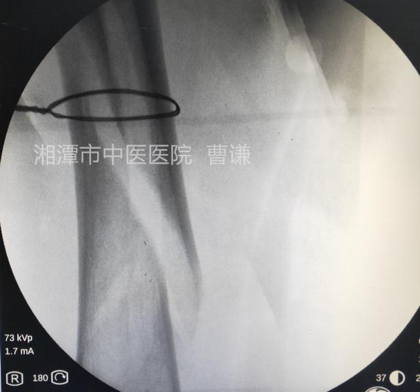

在助手维持牵引的同时,使用老虎钳将钢丝拧紧(注意尽量夹持到钢丝结头顶部并提起拧紧)

透视见钢丝逐渐拧紧并使骨折端靠近复位。

在远折端依前法再置入一根钢丝进行捆扎复位,因担心过度拧紧导致钢丝断裂,没有强求骨折解剖复位。